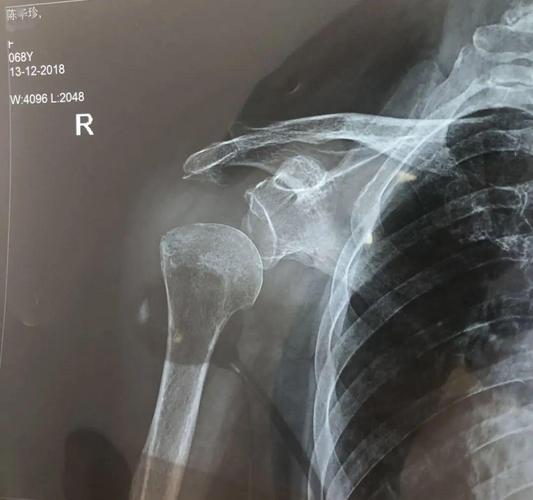

肩关节脱位x线

肩关节脱位x线图片